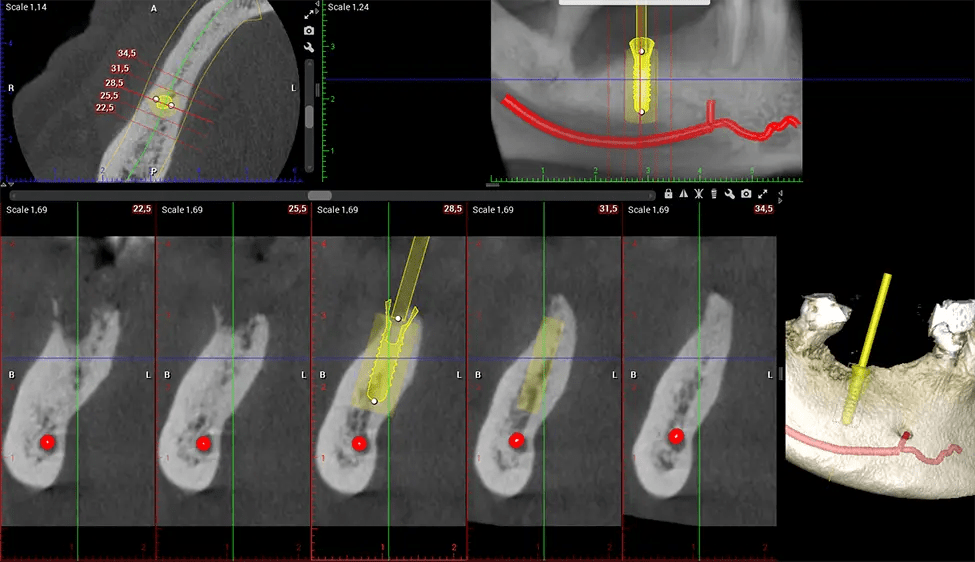

When paired with extractions, dental implant placement, or bone grafting, CBCT technology can provide you with a quicker and much more comfortable experience. This is because the 3D image provides a more detailed picture of your entire oral cavity, allowing your dentist to walk you through each step of the process before it occurs. This often helps patients feel more prepared and comfortable overall, especially if they have had a traumatic experience with past dental treatments.

After the scanning process, the captured X-ray images are processed by the CBCT software, which applies algorithms to reconstruct a detailed 3D image of the scanned area. The software compiles these individual X-ray images and creates a digital 3D representation of the patient’s anatomy. The reconstructed 3D CBCT image can be viewed and analyzed by the dentist or radiologist. This image can be manipulated, rotated, and zoomed in or out to examine specific structures and evaluate the patient’s condition.